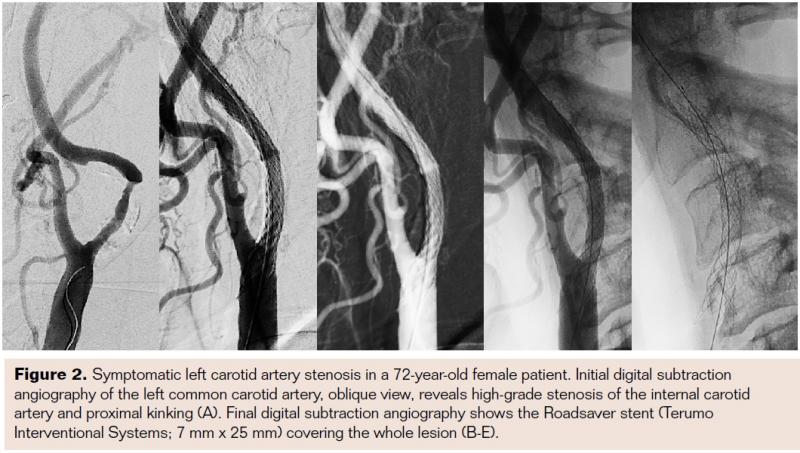

In addition to these first clinical data and experience with the Roadsaver stent, it is necessary to clarify that a certain learning curve for safe and accurate stent placement is warranted. This is because experience is needed to predict the stent length. It is highly recommended to start with larger diameters or longer stent lengths in order to achieve good lesion covering. In Figures 1-3 the Roadsaver stent is shown in 3 different anatomical locations.

The Roadsaver stent (Terumo Interventional Systems) currently is the only FDA-approved, CE-marked, commercially available double-layer micromesh stent. This self-tapering stent is composed of two nitinol (nickel titanium) interwoven mesh layers, creating a flexible scaffold. The inner mesh has an extremely small cell size (0.381 mm2), which is designed to prevent release of emboli. The internal fine meshwork should prevent plaque prolapse.17 A number of micromesh cells fit into one macromesh cell, acting like a metallic covered stent.

The device is compatible with a 5 Fr sheath or 6 Fr guiding catheter. Up to the point of 50% deployment, the push-and-pull stent delivery system is full resheathable and repositionable. The low profile (5 Fr) enhances the crossability for primary stenting. The double-layer micromesh scaffold should enable sustained embolic protection by tight plaque coverage. The feasibility, efficacy, and safety of performing carotid angioplasty and stenting with the Roadsaver stent has been demonstrated in two studies.15,16 Kedev et al used transradial slender 5 Fr techniques to implant the Roadsaver stent in the left and right carotid arteries with promising results.16